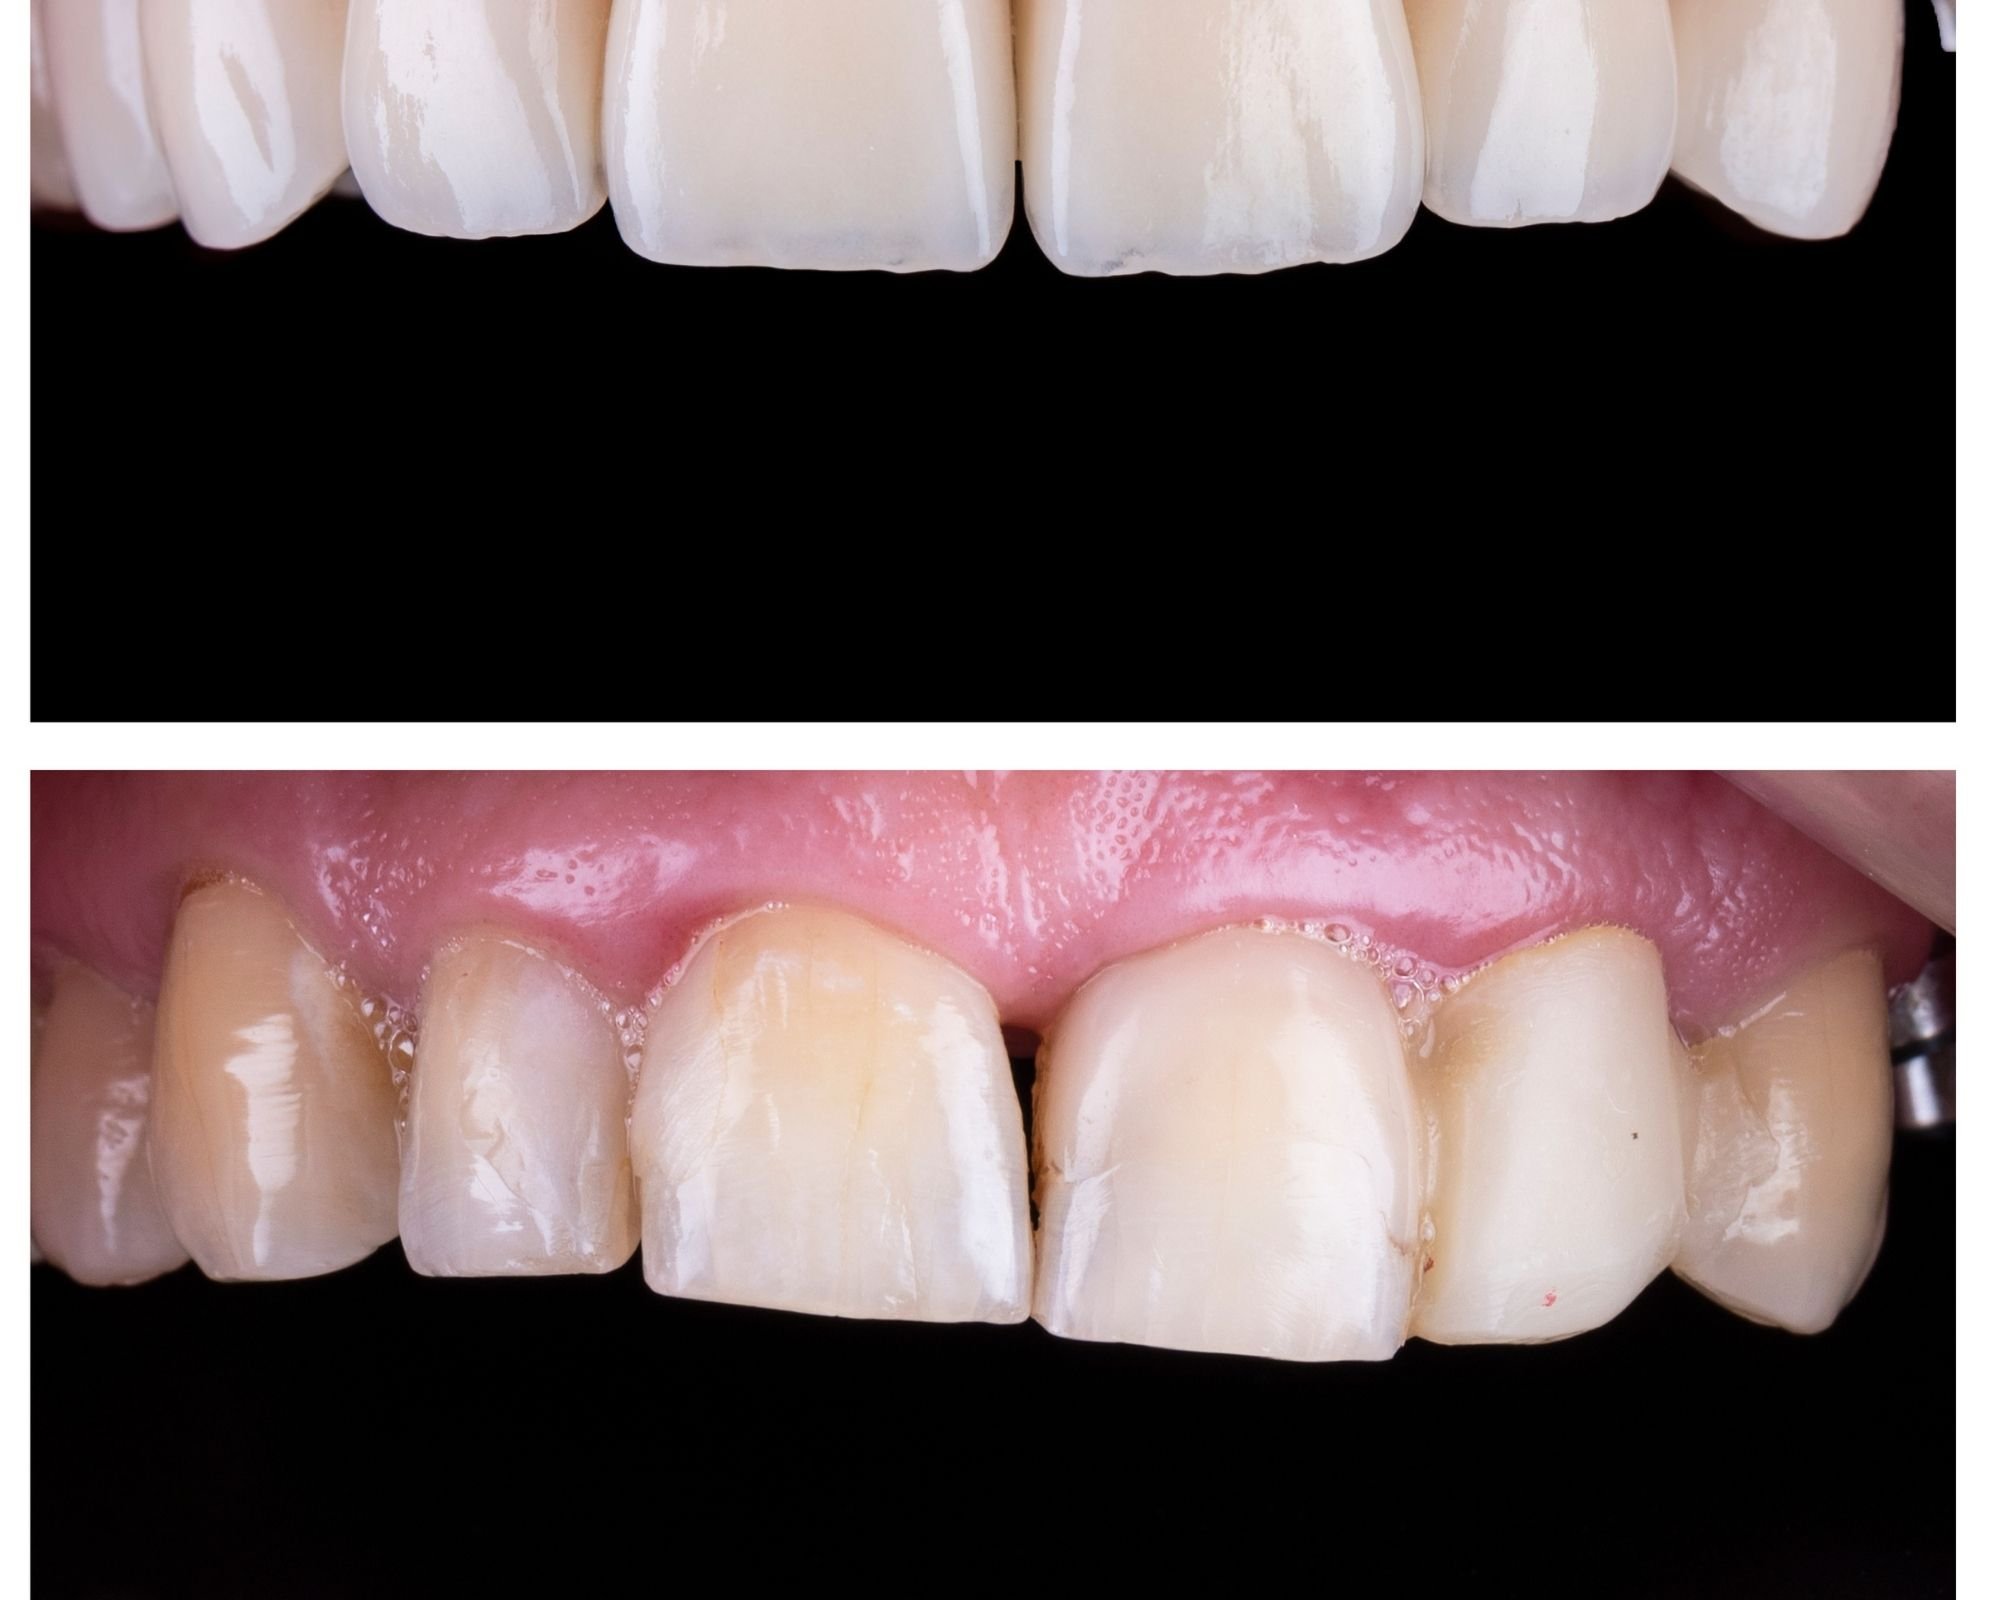

Root Canal Before & Afters Midtown Endodontist NYC How To Relieve Pain Before Root Canal Treatment Web if you’ve had a root canal procedure and your gums still hurt, there are a few home remedies you can try to reduce. Endodontists and dentists do about 15 million root canals in the united. Web managing root canal pain involves adopting several strategies to alleviate discomfort and promote a smoother. Alternate hot and cold compresses on. Web soak. How To Relieve Pain Before Root Canal Treatment.

Root Canal Before & Afters Midtown Endodontist NYC How To Relieve Pain Before Root Canal Treatment Alternate hot and cold compresses on. Endodontists and dentists do about 15 million root canals in the united. Web managing root canal pain involves adopting several strategies to alleviate discomfort and promote a smoother. Web a root canal is treatment for infections in tooth pulp, the innermost layer of your teeth. Web soak a cotton ball with apple cider vinegar. How To Relieve Pain Before Root Canal Treatment.